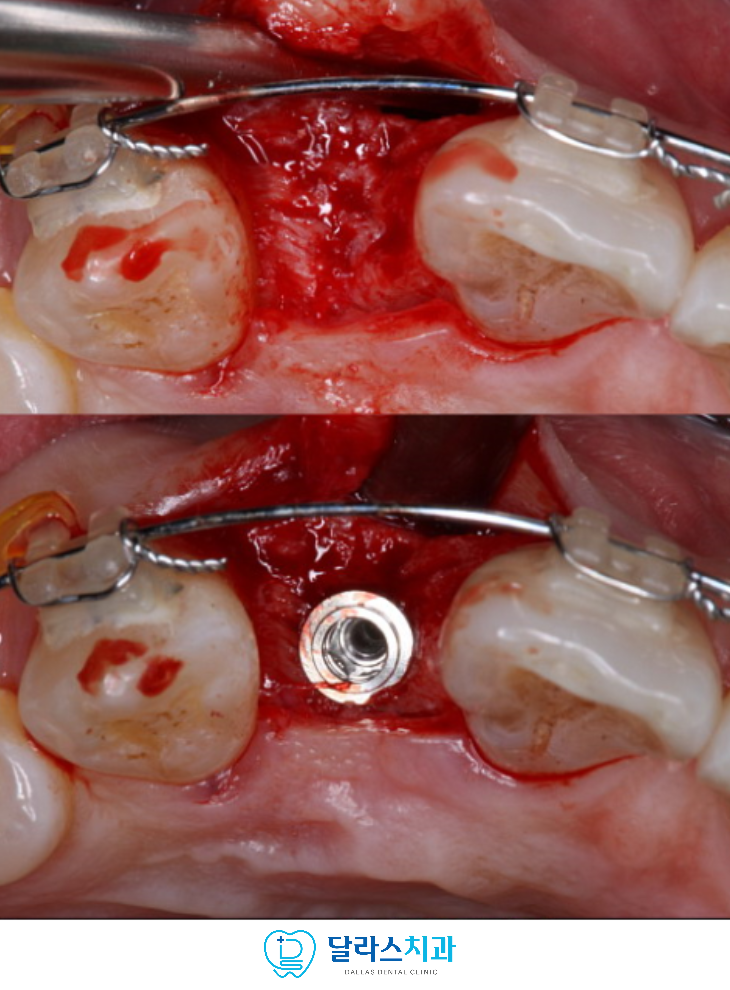

식립하면서 육안으로 확인한 결과 기존에 유치를 발치하고

공간을 확보한 입술쪽 부분에 치조골이 부족한 것을 확인하였습니다.

임플란트의 안정적인 골유착을 위해서

입술쪽에 치조골을 이식하였습니다.